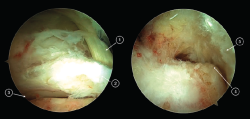

Los portales endoscópicos posteriores de tobillo (posteromedial y posterolateral) se localizan al mismo nivel de la punta del peroné o ligeramente distales a ambos lados del tendón de Aquiles. Se utiliza el portal posterolateral como portal de la visión y el portal posteromedial como portal de trabajo. La técnica endoscópica sigue inicialmente los pasos descritos por Van Dijk(10). La fascia de Rouviere y Canela debe abrirse para acceder a las estructuras de la región posterior del tobillo. Es importante que durante la creación del área de trabajo, la fascia de Rouviere y Canela se abra hacia proximal con el objetivo de evitar la flexión del tendón del FHL cuando este sea transferido hacia el calcáneo. Después de crear un área de trabajo, se identifican las estructuras anatómicas del tobillo a nivel de su región posterior (Figura 1). El tendón del músculo FHL es la principal referencia endoscópica, marcando el límite de seguridad de la zona de trabajo, ya que el paquete neurovascular tibial está situado justo medial al tendón FHL.

Figura 1. Tobillo izquierdo. Visión endoscópica de la región posterior del tobillo (imagen izquierda). 1: tendón del flexor hallucis longus (FHL); 2: proceso posterior del astrágalo (Stieda); 3: articulación subastragalina. Redirigiendo el artroscopio y su visión hacia posterior puede observarse (imagen de la derecha) el tubérculo posterior del calcáneo (4) y la cara anterior del tendón calcáneo (5).